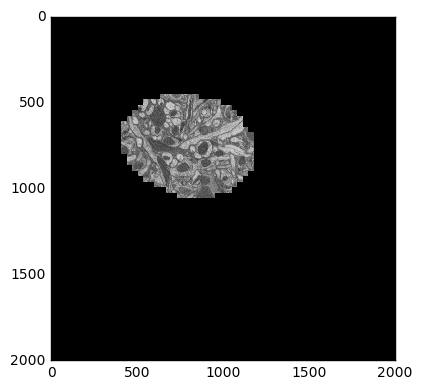

This data is from drosophila: http://emdata.janelia.org/. Here is an example 2d slice of the data http://emdata.janelia.org/api/node/bf1/grayscale/raw/xy/2000_2000/1800_2300_5000.

import skimage.io

import matplotlib.pyplot as plt

sample = skimage.io.imread('http://emdata.janelia.org/api/node/bf1/grayscale/raw/xy/2000_2000/1800_2300_5000'

skimage.io.imshow(sample)

The last number in the URL is an index into a large stack of about 10000 images. We can change that number to get different slices through our 3D dataset.